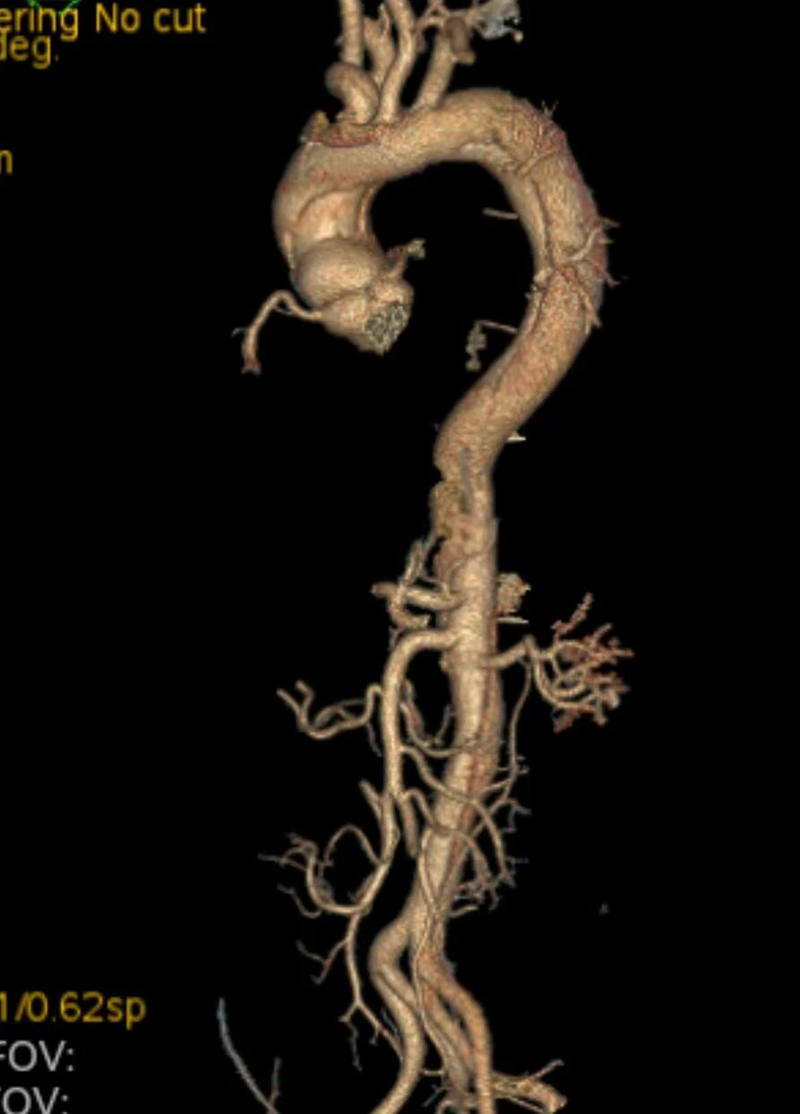

术前检查

与死神赛跑,多学科协作创造生命奇迹。主动脉是人体最粗大的动脉血管,一旦发生夹层撕裂,死亡率极高。A型主动脉夹层尤为凶险,发病后每小时死亡率增加1-2%,48小时内死亡率高达50%,堪称“人体炸弹”。此次救治的8例患者年龄在34至58岁之间,均为高血压患者且血压控制不理想,均以突发剧烈胸背部刀割样疼痛就诊。面对这一严峻挑战,我院立即启动“主动脉夹层绿色通道”,急诊科、医学影像科、心脏血管外科、麻醉科、手术室、输血科、重症医学科等多学科团队紧密协作,在24小时黄金救治时间内完成诊断和手术准备。

在手术中,心脏血管外科团队为5例A型夹层患者成功实施“孙氏手术”等顶级复杂术式,在深低温停循环条件下完成升主动脉及主动脉弓的精准替换与重建;对3例B型夹层患者则采用“主动脉覆膜支架腔内修复术”,通过微创介入成功隔绝夹层破口。这两类手术的成功开展,彰显了我院在主动脉疾病全谱系救治方面的成熟技术。